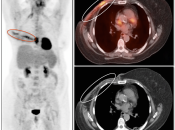

- Post-Therapeutic Scar vs. Active Malignancy

- Assess Response to Therapy

Post-Operative Inflammatory Changes

Post-surgical inflammatory changes can present a diagnostic challenge for the PET/CT radiologist.

Very commonly, surgery results in ill-defined inflammatory soft tissue density in the operative bed, which can be difficult to distinguish from residual or recurrent malignancy. Further complicating matters, this post-operative inflammatory soft tissue is often intensely FDG-avid.

During the first weeks following surgery, distinguishing this ill-defined hypermetabolic inflammatory soft tissue from residual or recurrent malignancy can be exceedingly difficult. Frequently, only a follow up exam will permit this distinction: